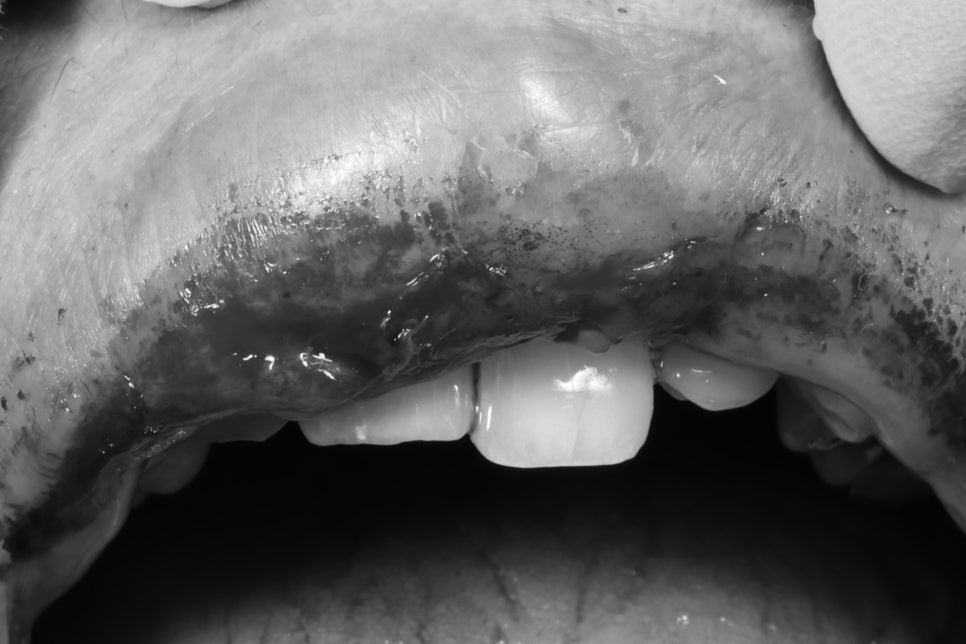

첫날 오셨을 때 이렇게

치아가 약간 빠진 채로 오셔서

일단 마취 후에

치아를 재위치 시키고, 고정시키고

입술도 처치를 해드리고

진통제 처방 후에

귀가시켜 드렸던 기억이 납니다.